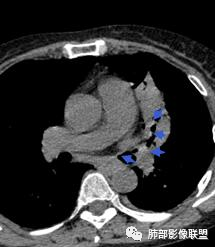

左肺团块影,形态不规则,其内见充气支气管征,增强扫描明显强化,其内见液化坏死区。下叶基底段见斑点状密度增高影。双肺门见斑点状钙化影。疾病谱有结核,增强除外了。肺癌和淋巴瘤鉴别。

病灶远端有扩张支气管,树芽,实变,纵隔肺内淋巴结钙化,考虑肺结核。

整个上叶尖后段阻塞性肺不张的表现,从强化来看没有异常结节状或肿块样强化,肿块内部点状钙化、纵隔多发小淋巴结、下叶背段有树芽征,整体来看支持肺结核,让人不放心的是最后一幅冠状位重建的图像尖后段支气管堵了,而且有轻度的隆起,所以很难除外粘液表皮样癌(女性,鳞癌可能性小),如果是我写报告肯定会建议纤支镜检查

中年女性,反复咳嗽咳痰4月,加重半月,咳嗽,咳黄痰。胸CT:左肺体积缩小,左肺上叶病变,病灶内可见支气管征,病灶边缘可见棘突样改变,病灶周围可见结节状卫星灶,纵隔可见淋巴结肿大,部分淋巴结可见钙化灶。增强CT病灶内可见低密度坏死区,冠状位病灶内支气管可见扩张,病灶整体呈收缩,考虑患者为良性慢性感染性病变,结核?放线?,建议支气管镜检查。

考虑结核伴混合感染。中青年女性,持续低热、不正规抗感染症状加重。左上肺低密度肿块,左上固有段支气管未显影(结核侵蚀干酪样坏死),左上舌段支气管通畅但增厚变形。左下肺树芽征新发支气管播散。鉴别:粘液腺癌

左上叶实变不张,膨胀生长,上叶开口阻塞?,病灶内支气管扩张,明显延迟强化,内见低密度灶及点状钙化,周边见小叶间隔增厚丶结节,右斜裂结节

看这些钙化

前壁不厚,附近钙化灶太多,所以觉得结核一定要考虑,加上树芽征,就更支持。

支气管壁软骨存在且连续,没有被破坏掉,支气管壁局部通畅,提示支气管壁没破坏,那么近端支气管癌肿不考虑。远端有树丫征,病灶周围很多钙化,所以结核一定有。